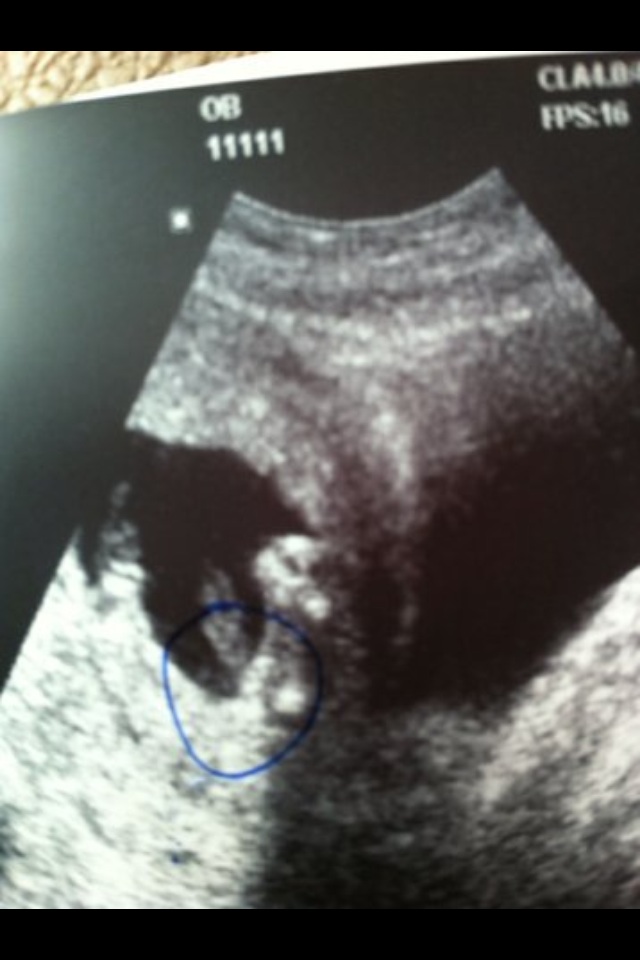

16 week ultrasound-swayed girl